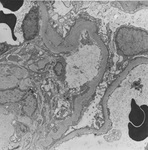

Doença renal diabética

Doença renal diabética: na posição de 5 horas - nódulo de Kimmelstiel-Wilson no início, um aumento arredondado na matriz mesangial que provavelmente foi originado em relação a um microaneurisma

Do acervo do Dr. Raoul Fresco; usado com permissão